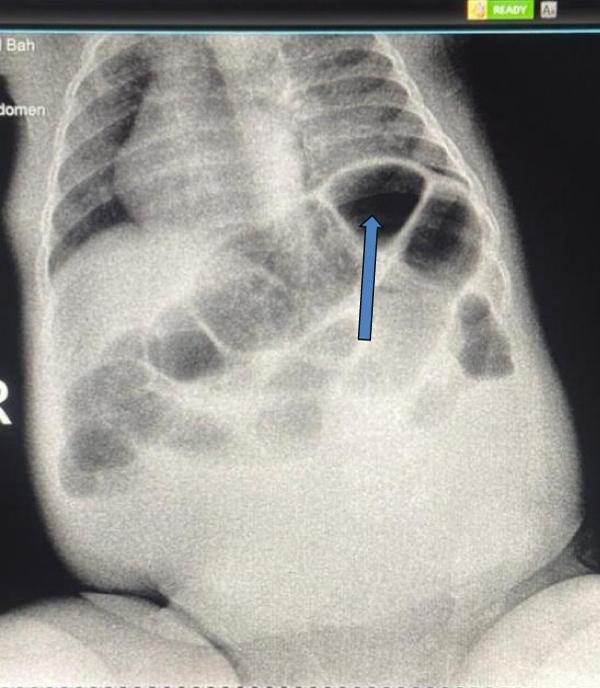

A stool examination revealed bloody stools by the third day of symptom onset. Laboratory results showed a leukocyte count of 6.8 × 109/L and hemoglobin of 7.8 g/dL (indicating moderate anemia). Mild hypokalemia of 3.06 mmol/L was noted, likely due to vomiting. A rapid point-of-care diagnostic test for Respiratory Syncytial Virus (RSV) was positive, confirming the viral etiology for the respiratory symptoms. Erect abdominal X-ray showed signs of intestinal obstruction, including dilated bowel loops and air-fluid levels, raising suspicion for intussusception (Figure 1). A diagnostic ultrasound confirmed the diagnosis.

Download Image

Figure 1: Abdominal X-ray showing signs of intestinal obstruction (dilated bowel loops, air-fluid levels-arrow).